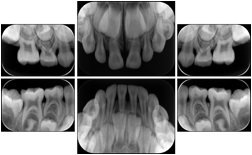

OO.1.2 Ophthalmology

1. A patient in rural Canada visits a general ophthalmologist and is found to have diabetic macular edema. The general ophthalmologist would like to discuss the case with a retina specialist before performing laser surgery. A fluorescein angiogram is done with multiple retinal images taken in a timed series after an intravenous injection. The images along with a Structured Display are shared via a Health Information Exchange with a retina specialist in Calgary, who opens them using his Ophthalmology EMR software and consults via phone with the general ophthalmologist. Both physicians view the images in the same layout so the retina specialist can provide accurate guidance for treating the patient.

2. A patient in rural Iowa visits his primary care physician for management of diabetes. Three non-mydriatic (patient's eyes are not dilated) photographs are taken of the back of each eye, and forwarded electronically along with a Structured Display to an ophthalmologist in Iowa City. The ophthalmologist reads the photos in an agreed upon layout so there is no mistake about what portion of which eye is being viewed. The ophthalmologist is able to tell the primary care physician that his patient does not need to come to Iowa City for face to face ophthalmologic care, but that there is a particular view of the left eye that should be photographed again in 6 months.

Ophthalmic Retinal Study Structured Display

Figure OO-3. Ophthalmic Retinal Study Structured Display

3. A patient in rural Minnesota experiences sudden vision loss and goes to a general ophthalmologist, who acquires OCT images and forwards them electronically along with a Structured Display to a retina specialist six travel hours away. The retina specialist is able to view the images in the standard layout that he is comfortable with, and to confirm that the patient has a choroidal neovascular membrane. He determines that is would be worthwhile for the patient to travel for treatment.